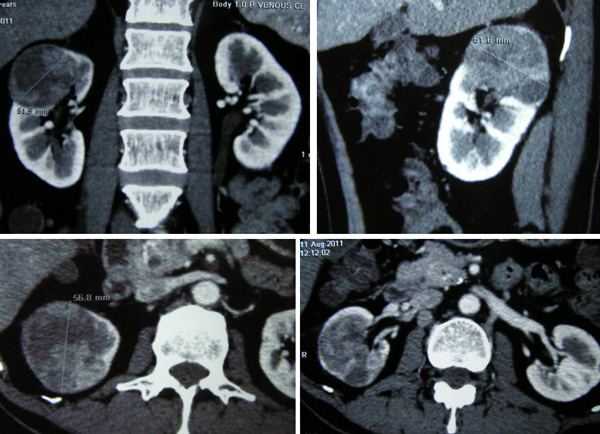

An ultrasound done on 8 August 2011 indicated a 1.3 x 1.6 cm cyst at the upper pole of his left kidney and a focal lesion, 4.8 x 4.4 cm at the upper pole of his right kidney. A CT scan done on 11 August 2011 confirmed the presence of a 5.2 x 5.7 x 5 cm solid tumour in the upper pole of his right kidney. There was a 1.5 cm cyst in the upper pole of his left kidney.